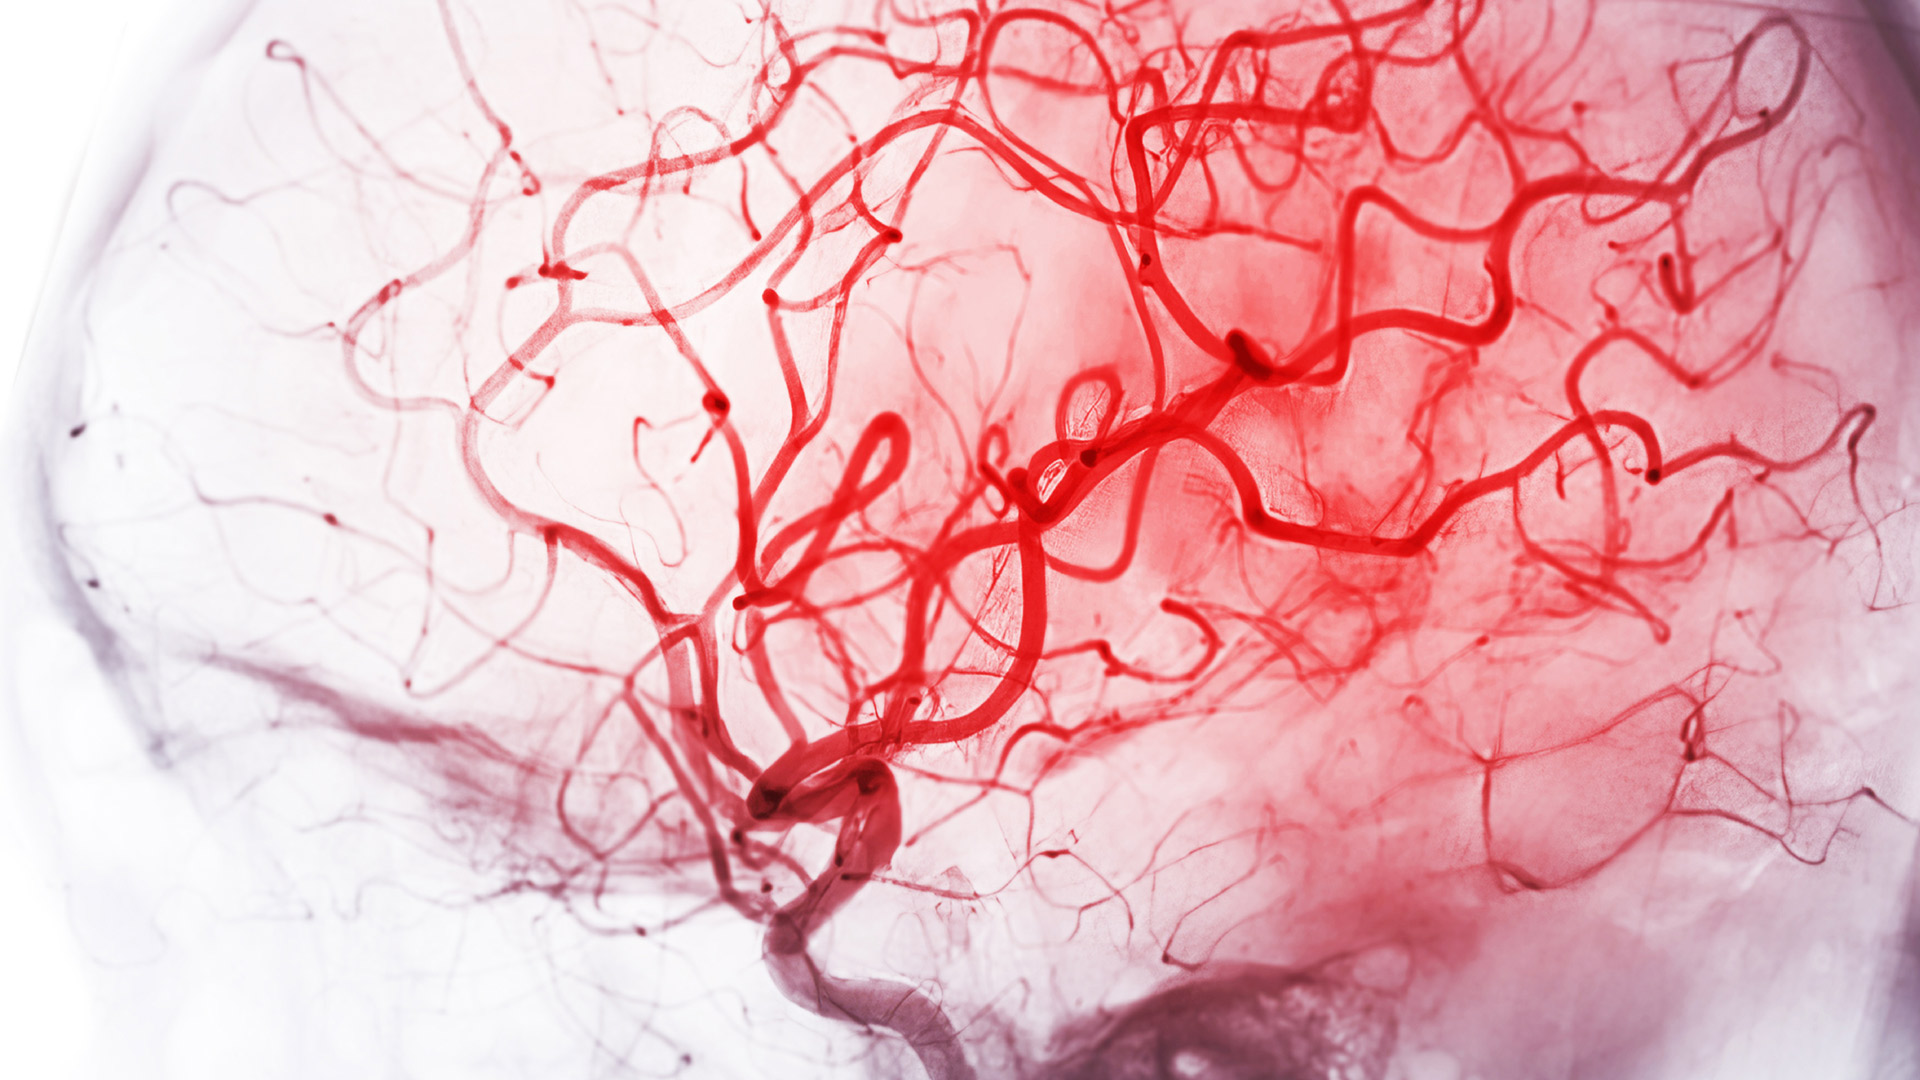

Heart attacks kill heart muscle cells, which the body cannot regenerate. These dead cells are replaced with non-functional scar tissue that can’t contract or pump blood properly, leading to long-term heart damage and heart failure in about a third of people.

The therapy uses messenger RNA (mRNA) - the same type of technology used in COVID-19 vaccines - to send healing instructions directly into the heart. These instructions are carried in tiny particles called lipid nanoparticles (LNPs), which help safely deliver the message to specific heart cells and activate only where needed.

The team has already demonstrated that their therapy can successfully reach and enter damaged heart tissue using in vitro models - a critical step toward regenerating the heart after a heart attack.